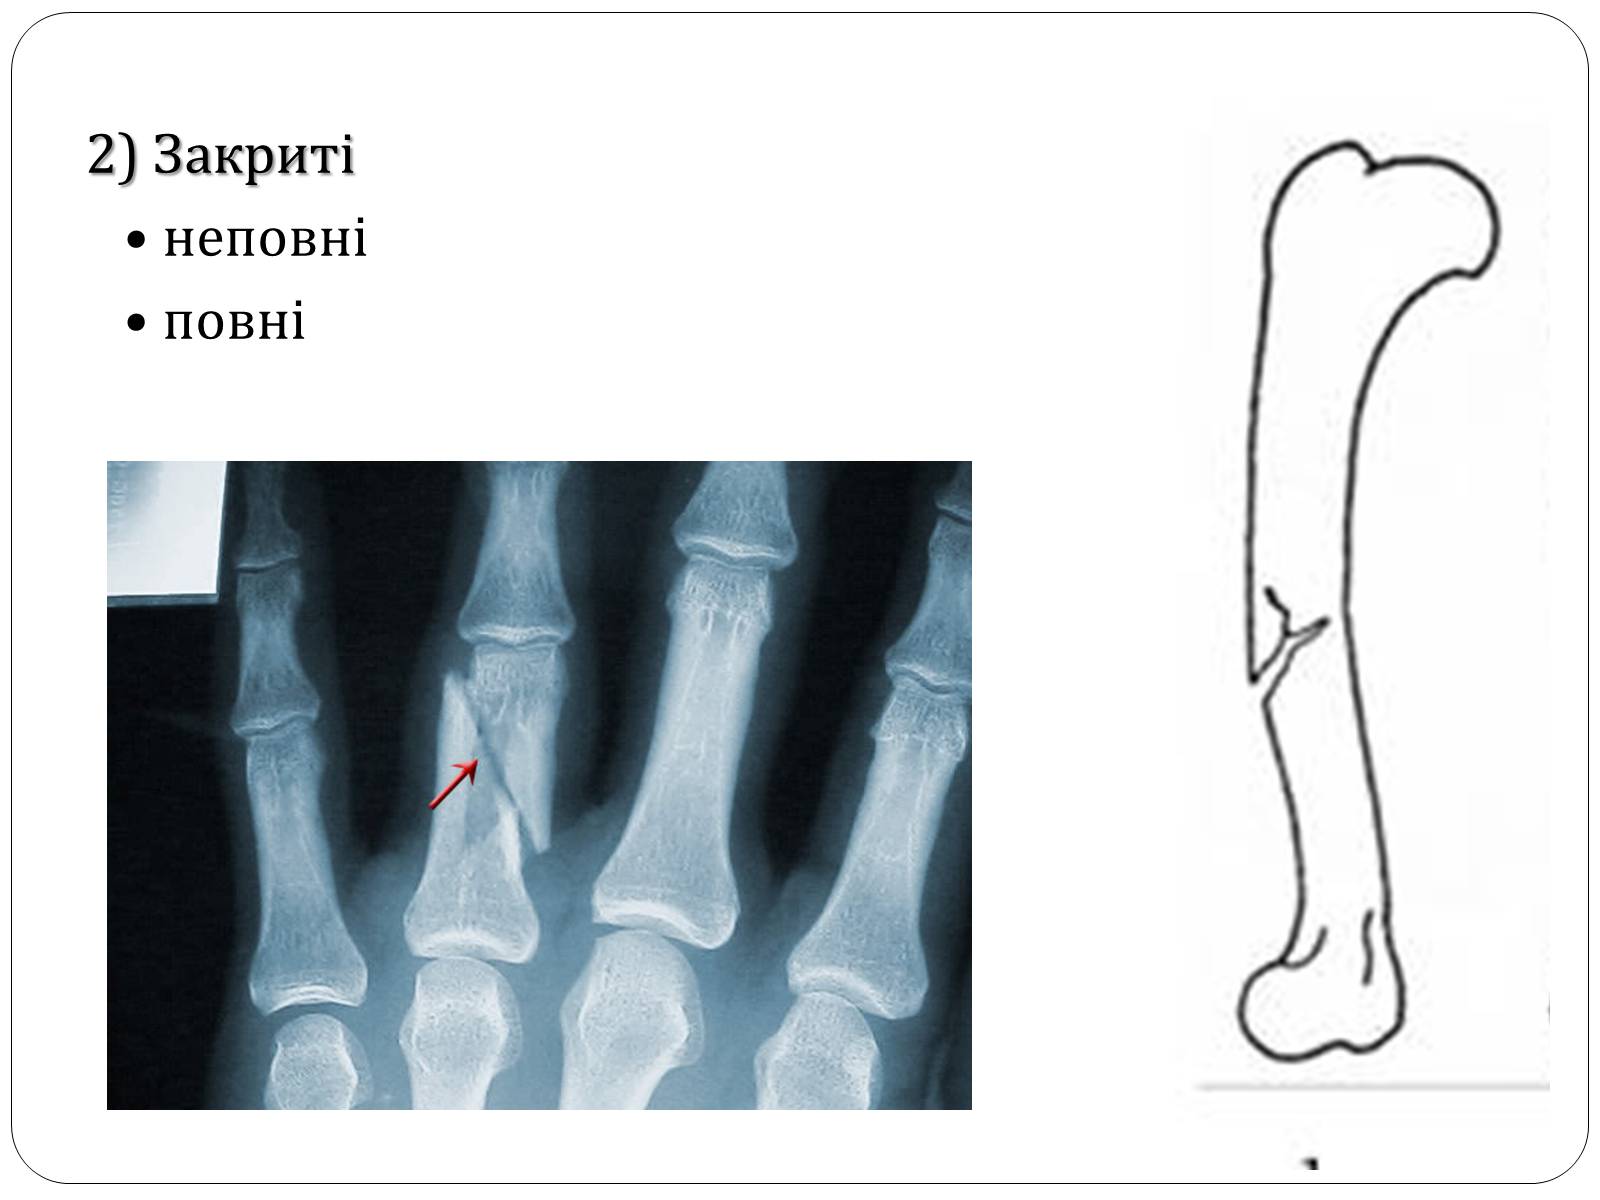

2) Закриті

• неповні

• повні